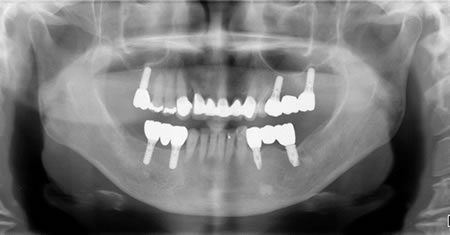

■治療後

先日 咀嚼障害と審美障害を主訴に来院された慢性歯周炎の患者さんの包括的治療が終わりました。入れ歯は選択枝から外され、固定性を強く希望されたので、包括的治療をおこないました。包括的治療とは、歯科治療において必要と思われるすべての治療(歯周病治療・根管治療・インプラント治療・矯正治療・補綴治療・咬合回復治療・審美歯科治療をおこない、咬み合わせの調和が達成できていることです。